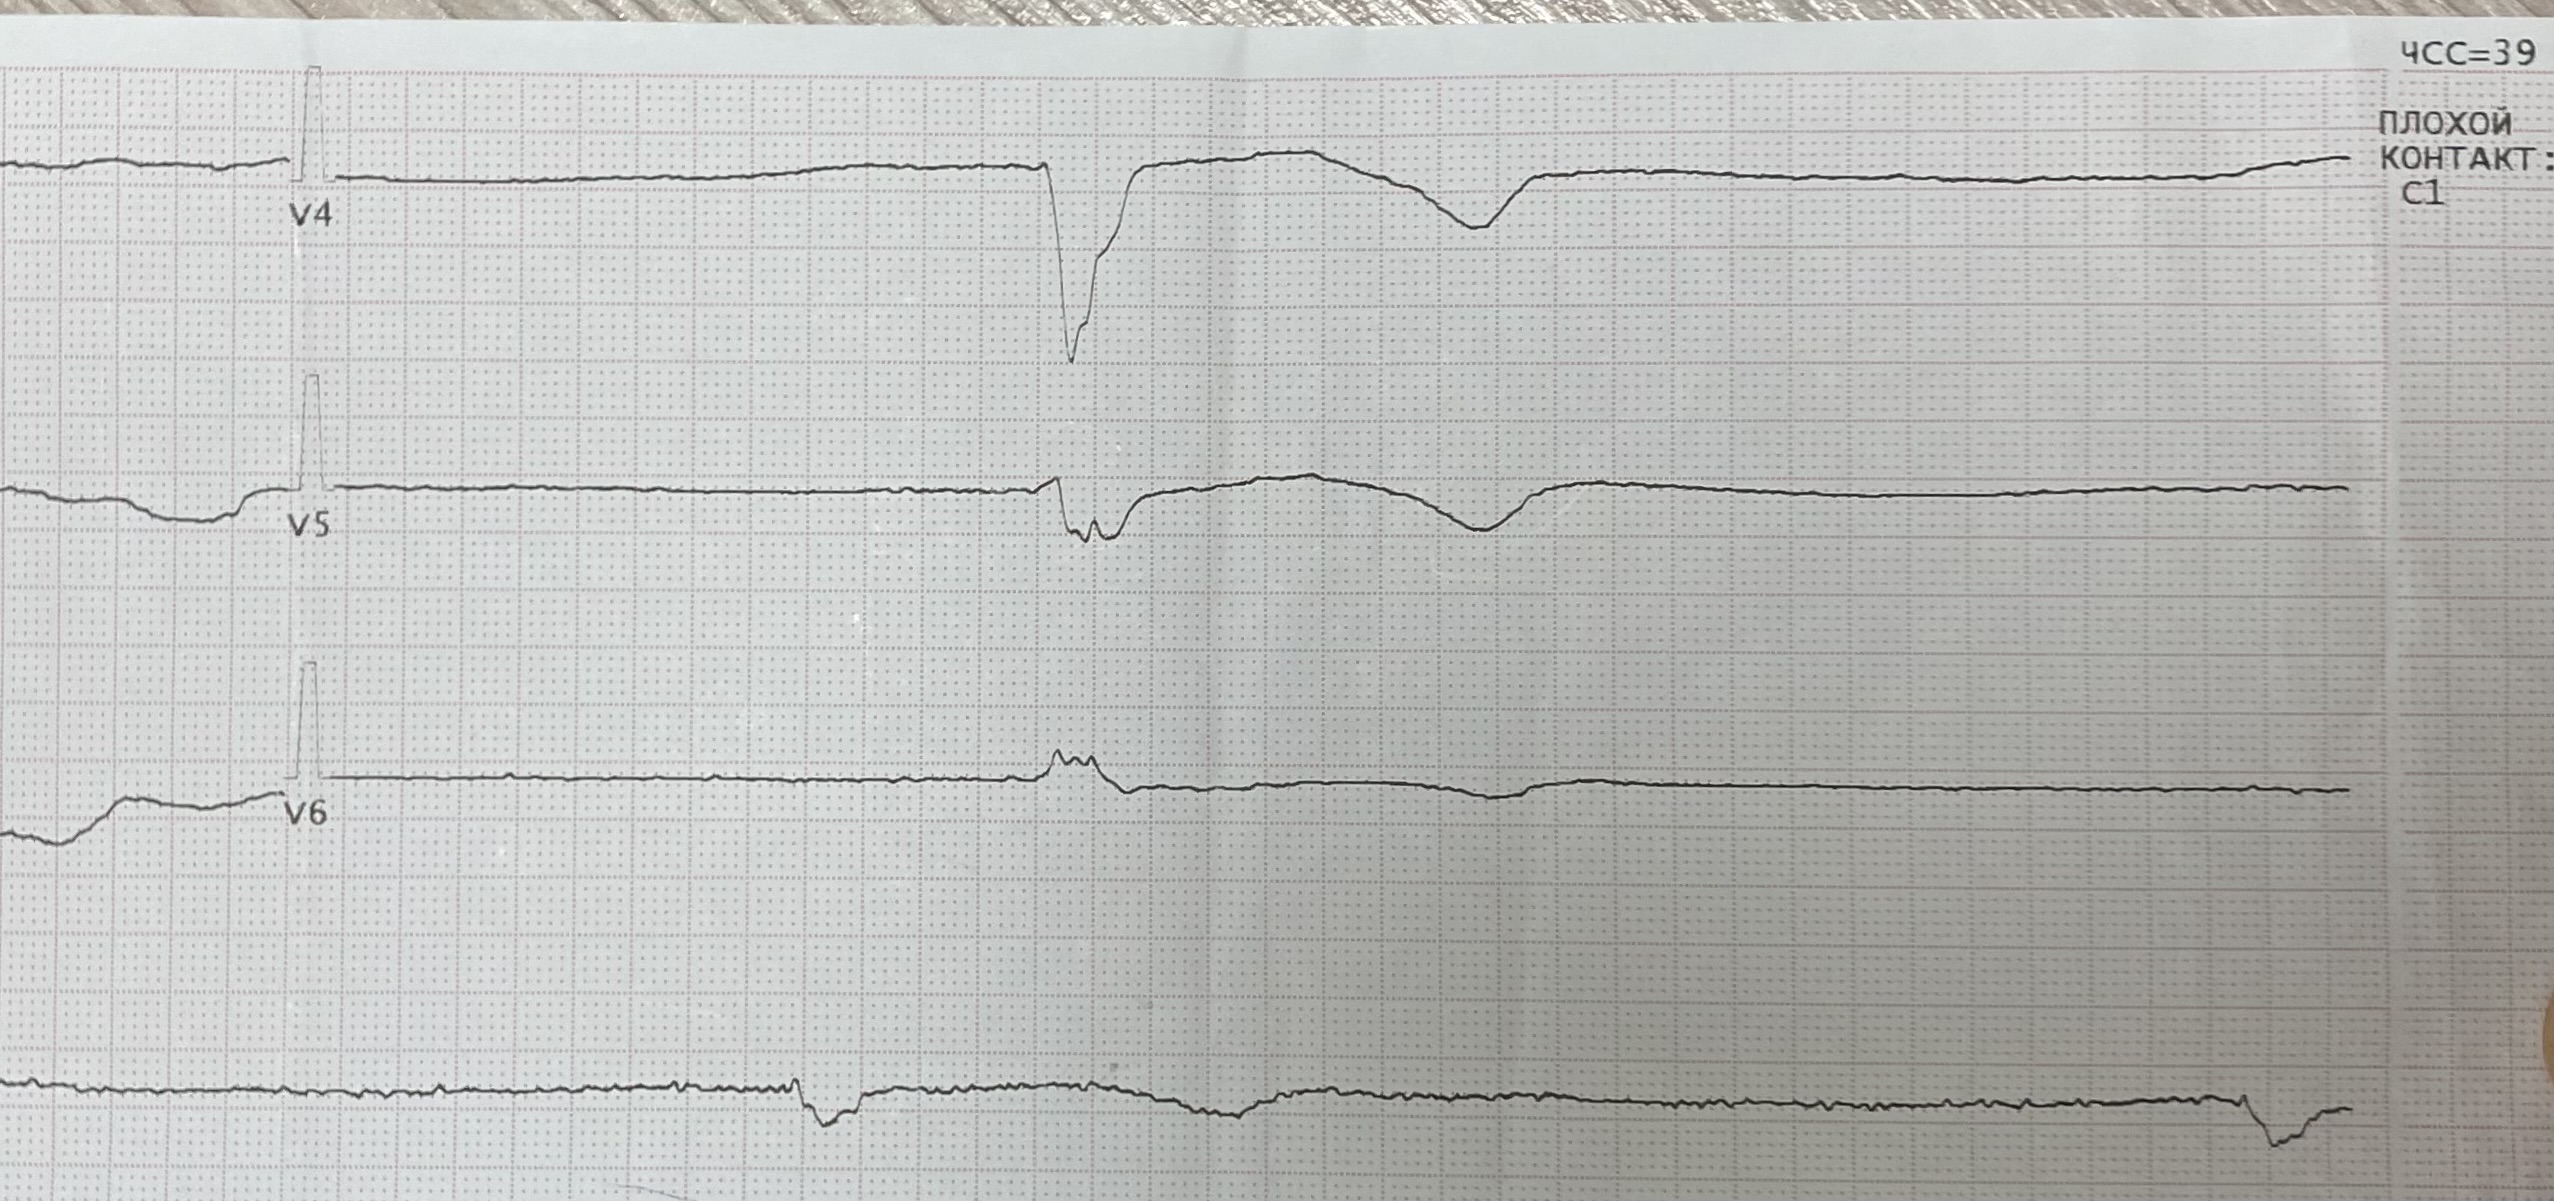

Заголовок сообщения: Синдром Фредерика

Обсуждалось здесь https://vk.com/club84409679?w=wall-84409679_13341%2Fall